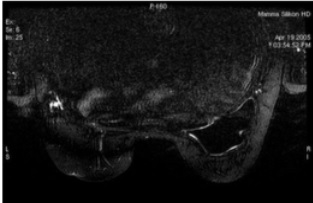

Figure 1. STIR with water SAT: Fat = dark, Water = dark, Silicone = bright

Figure 2. STIR: Fat = dark, Water = vrey bright, Silicone = bright

Figure 3. T2 no SAT: Fat = bright, Water = bright, Silicone = bright

Figure 4. FSE fat SAT: Fat = medium, Water = bright, silicone = dark

Figure 5. STIR with silicon suppressed: Fat = dark, Water = bright, Silicone = dark